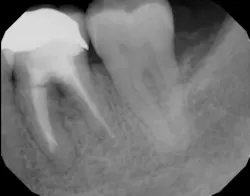

In other words, even experienced clinicians who access a root surface with flap surgery are sometimes limited in the amount of detoxification that can occur due to the depth of the defect and conventional instrumentation. (11) Further limitations with mechanical access to defects can come in the form of furcations with multirooted teeth. The diameter of the entrance to root furcation is usually smaller than the average tip of a curette, which can make access difficult (figures 1 and 1a). Molars with bone loss that includes furcations are often downgraded in prognosis due to this access difficulty. (12)

Figure 1: Molar with periodontal abscess due to furcation involvement

Figure 1a: Deep Class II furcation with an entrance smaller than the diameter of a curette tip